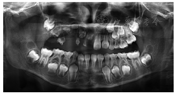

病例1:患者男性,2岁10个月,因"右侧面部反复肿胀,右侧上颌牙齿萌出延迟且形态异常"于2015年11月就诊于四川大学华西口腔医院预防科。既往史及家族史无特殊;口内检查见右侧牙龈红肿,51—55、85牙呈褐色,牙釉质发育异常,表面大量软垢。曲面体层X线片示51—55、16及85牙釉质和牙本质发育异常,牙体硬组织菲薄,密度较对侧同名牙低,髓腔宽大、牙根短、根尖孔敞开,呈"鬼影样"表现,右侧上颌恒前牙胚及前磨牙胚影像不清,病变累及整个右上象限区域牙及部分右下后牙区牙(图1A)。初诊医师建议转至儿童口腔科治疗,未见明确诊断及临床处置记录。

2年后,患者因"口内多颗虫牙"于四川大学华西口腔医院儿童口腔科就诊,口内检查见51、52缺失,53、54残根,55残冠,65、74、75、84、85龋坏,55、85表面形态不规则,釉质发育不完整。曲面体层X线片示右侧上颌恒牙胚影像较2年前清晰,与其他受累牙类似呈"鬼影样"改变(图1B)。诊断:65、74浅龋,75中龋,84深龋;55、85慢性根尖周炎;53、54残根。临床予65、74、75预防性树脂充填治疗,84预成冠修复、护髓充填治疗,85行冠髓切断并预成冠修复治疗,55根管治疗(试保留)。随访2个月,未诉不适。